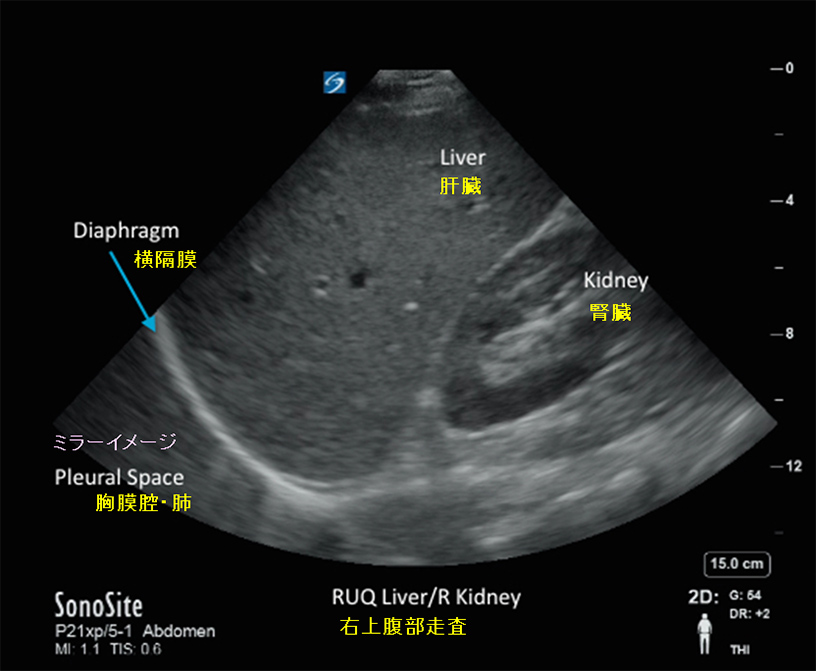

妊娠中の超音波スキャンでは、音波が胎児や体内の構造に反射して大まかな画像が作成されます。スキャンは写真ではないため、細部をすべてキャプチャすることはできません。

最も一般的なタイプは 2D 超音波で、シンプルでやや粗い白黒画像が得られます。